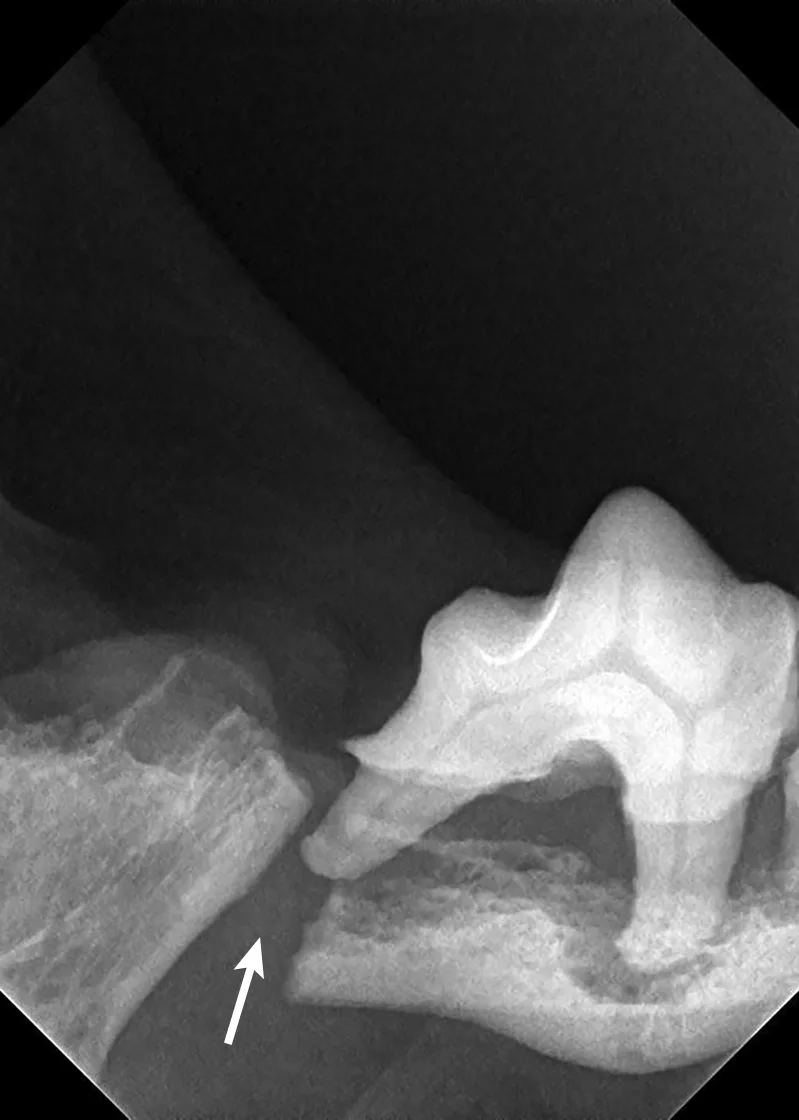

3. Jaw Fracture

Iatrogenic fracture of the jaw can be a serious complication of surgical extractions and is most commonly associated with surgical extraction of mandibular canine teeth in dogs and cats and mandibular first molar teeth in dogs (Figure 10). These extractions can be difficult to perform, as the root apexes are often located in close proximity to the ventral cortex of the mandible, possibly leading to significant bone loss when severe disease is present and increasing the risk for iatrogenic fracture (Figure 11).

Pathologic fracture (arrow) secondary to severe periodontal disease of the right mandibular first molar tooth in a dog

Severe periodontal disease affecting the right mandibular first molar tooth in a dog. Careful extraction technique is necessary to extract the tooth without creating an iatrogenic fracture.

Preoperative intraoral radiographs are critical for assessing fracture risk, especially prior to surgical tooth extraction, and can be used to modify the procedure or refer a patient with high fracture risk to a board-certified veterinary dentist.